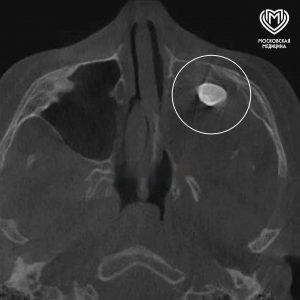

Московские врачи удалили зуб, который обнаружился в носу у подростка. Это оказалось редкой тератомой. Подробности уникального случая...